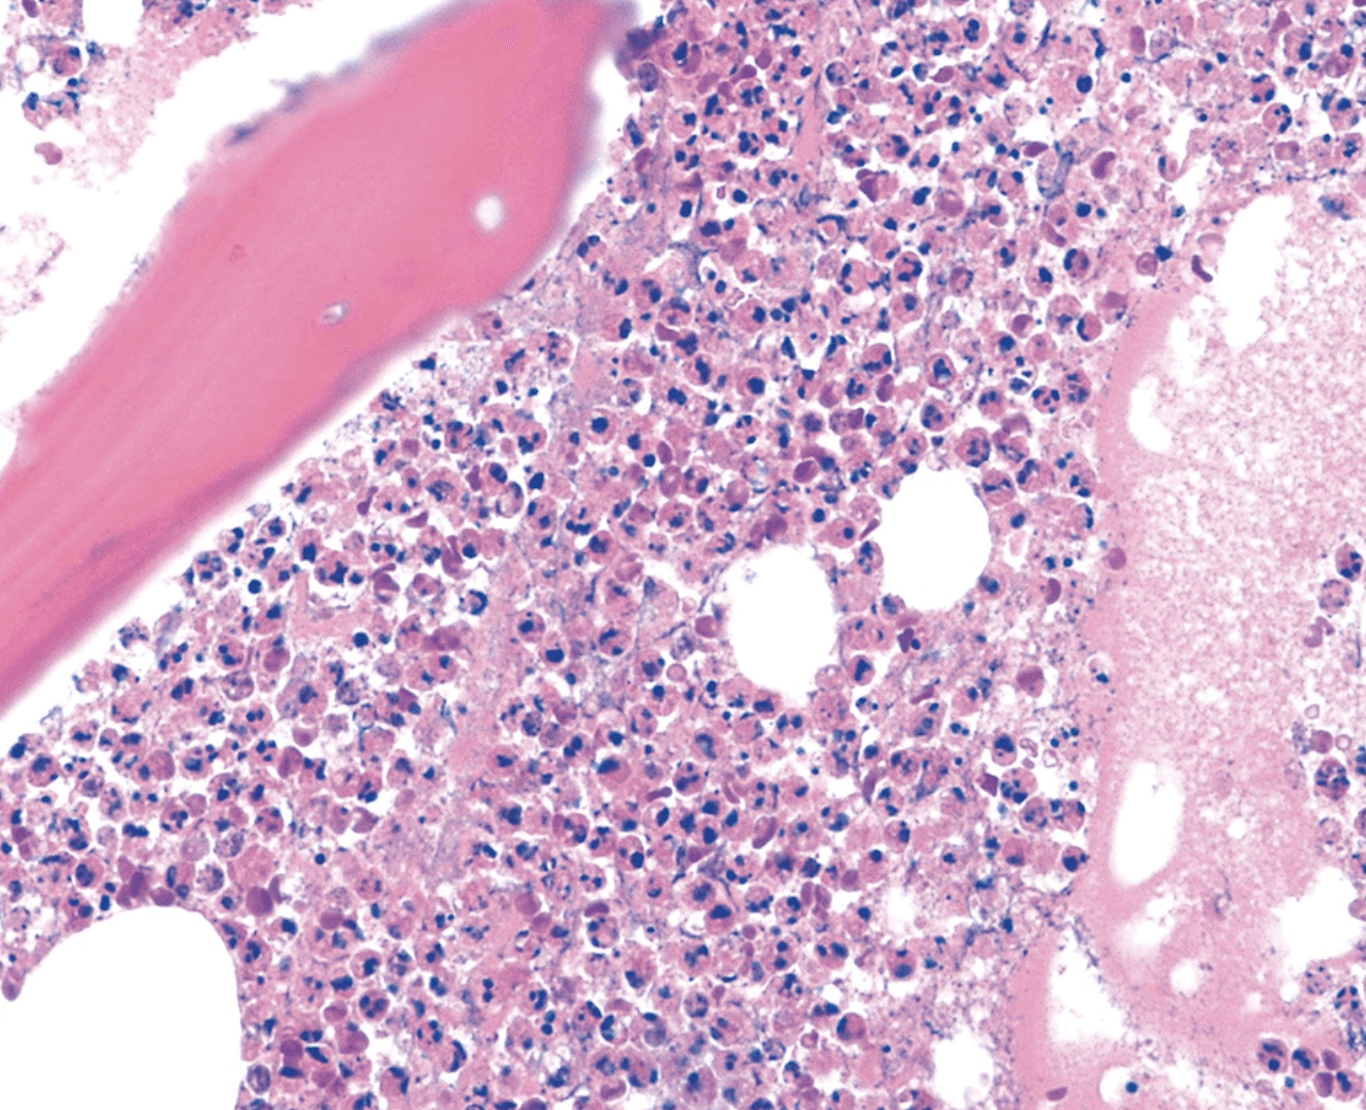

Laboratory studies: WBC 12.4 k/mcL with 78% neutrophils, hemoglobin 11.8 g/dL, platelets 340 k/mcL. CRP 42 mg/L, ESR 58 mm/hr. Random glucose 284 mg/dL. Plain radiographs show cortical erosion and periosteal reaction of the first metatarsal. MRI confirms osteomyelitis with a 3-cm abscess tracking along the plantar fascia. The patient undergoes transmetatarsal amputation with intraoperative bone biopsy from the proximal margin, shown below.

Proximal margin bone biopsy from transmetatarsal amputation: acute osteomyelitis with inflammatory infiltrate and bone destruction.